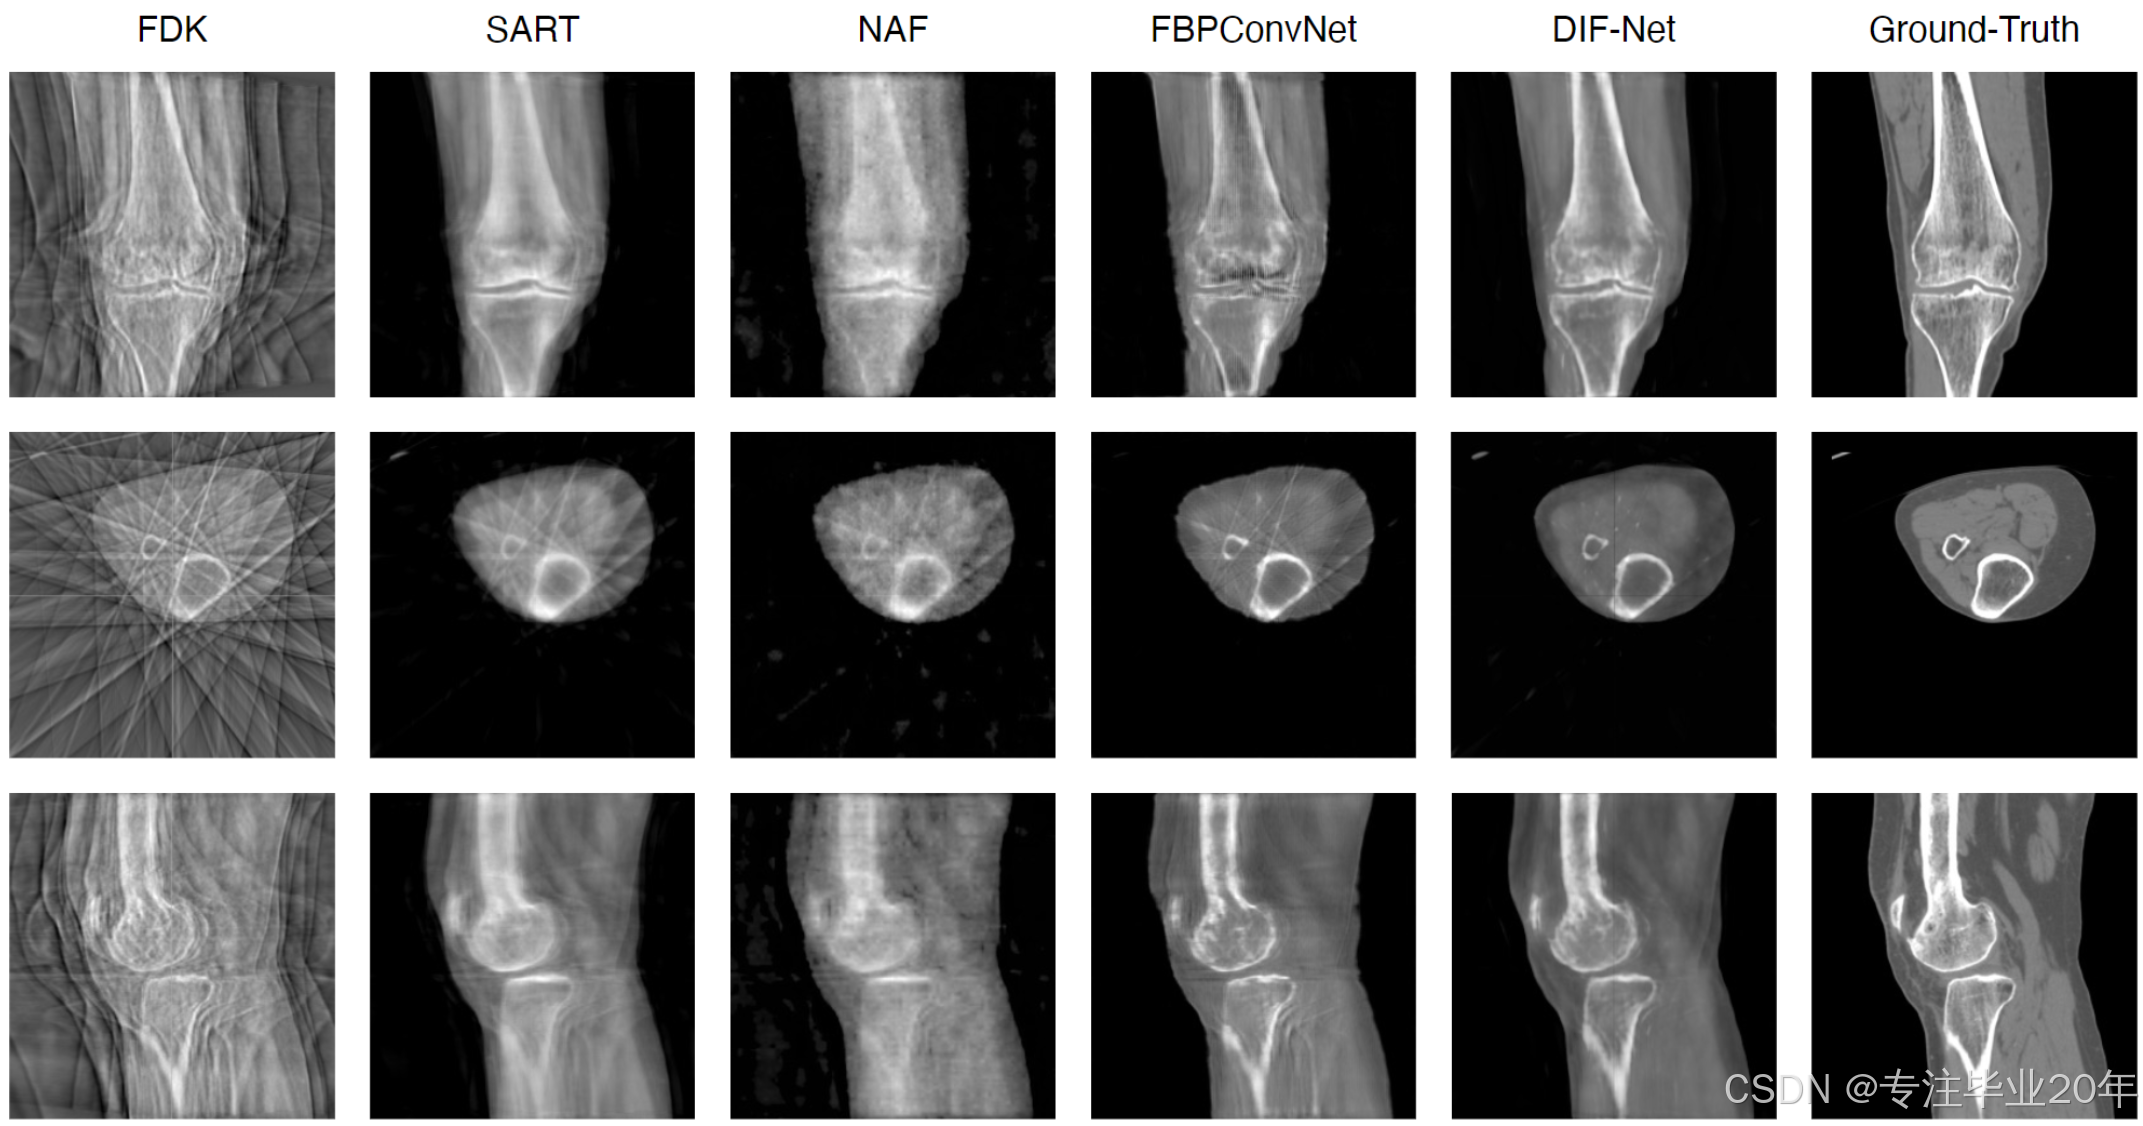

如表1所示,我们将DIF-Net与四种先前的方法 12 10 21 19 进行了比较,比较设置包括使用不同输出分辨率(即 12 8 3 , 25 6 3 128^3, 256^3 1283,2563)和不同数量的投影视图(即6、8和10)。实验表明,我们提出的DIF-Net即使只使用6个投影视图,也能重建出高质量的CBCT图像,在PSNR和SSIM值方面显著优于以往的工作。更重要的是,DIF-Net可以直接用于重建不同输出分辨率的CT图像,而无需重新训练或修改模型。如图3所示的视觉结果所示,FDK 10 由于缺乏足够的投影视图,产生了许多条纹伪影;SART 12 和NAF 19 产生了具有良好形状轮廓的结果,但缺乏详细的内部信息;FBPConvNet 25 重建了良好的形状和适中的细节,但仍然存在一些条纹伪影;而我们提出的DIF-Net能够重建高质量的CT图像,具有更好的形状轮廓、更清晰的内部信息和更少的伪影。更多关于输入视图数量的视觉比较请参见补充材料。

图3. 10视图重建的定性比较。